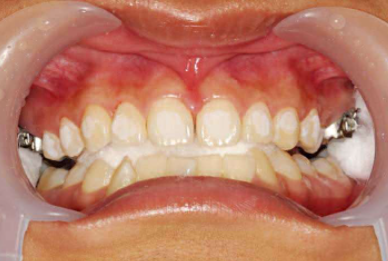

1、粘托槽的时候,如果无法明确判断牙齿的三维形态,可以把石膏模型放在旁边。最好在粘托槽之前,仔细分析石膏模型,观察牙齿的三维形态。一定要从颌面检查托槽是否在牙齿的近远中向的中心位置,可以利用口镜在口内从颌面观察托槽位置。必要时,也可以根据全景片明确牙体长轴(图1,图2)。

2、双尖牙的托槽要与牙长轴一致,垂直向位置应该在临床冠中心偏向龈方(图3,图4)。

3、前牙3-3,托槽的垂直高度应该在临床冠中心,但是同时还要彼此高度协调(表1-1)。